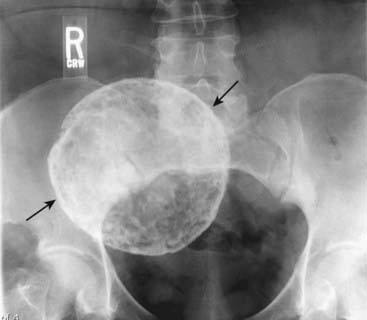

image

Figure 16-13 Calcified rim in uterine leiomyoma.

This is a rimlike calcification in the pelvis of a female patient (solid black arrows), so that it would be appropriate to consider that this calcification formed in the wall of a hollow viscus or saccular structure. In fact, this is a characteristic pattern of calcification in the outer wall of a degenerated uterine leiomyoma (fibroid). Cystic lesions of the ovary might produce this appearance, and ultrasound of the pelvis would be the study of choice to identify the organ of origin.